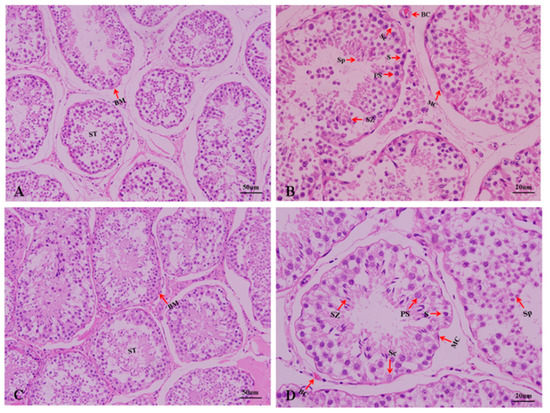

Show Figures